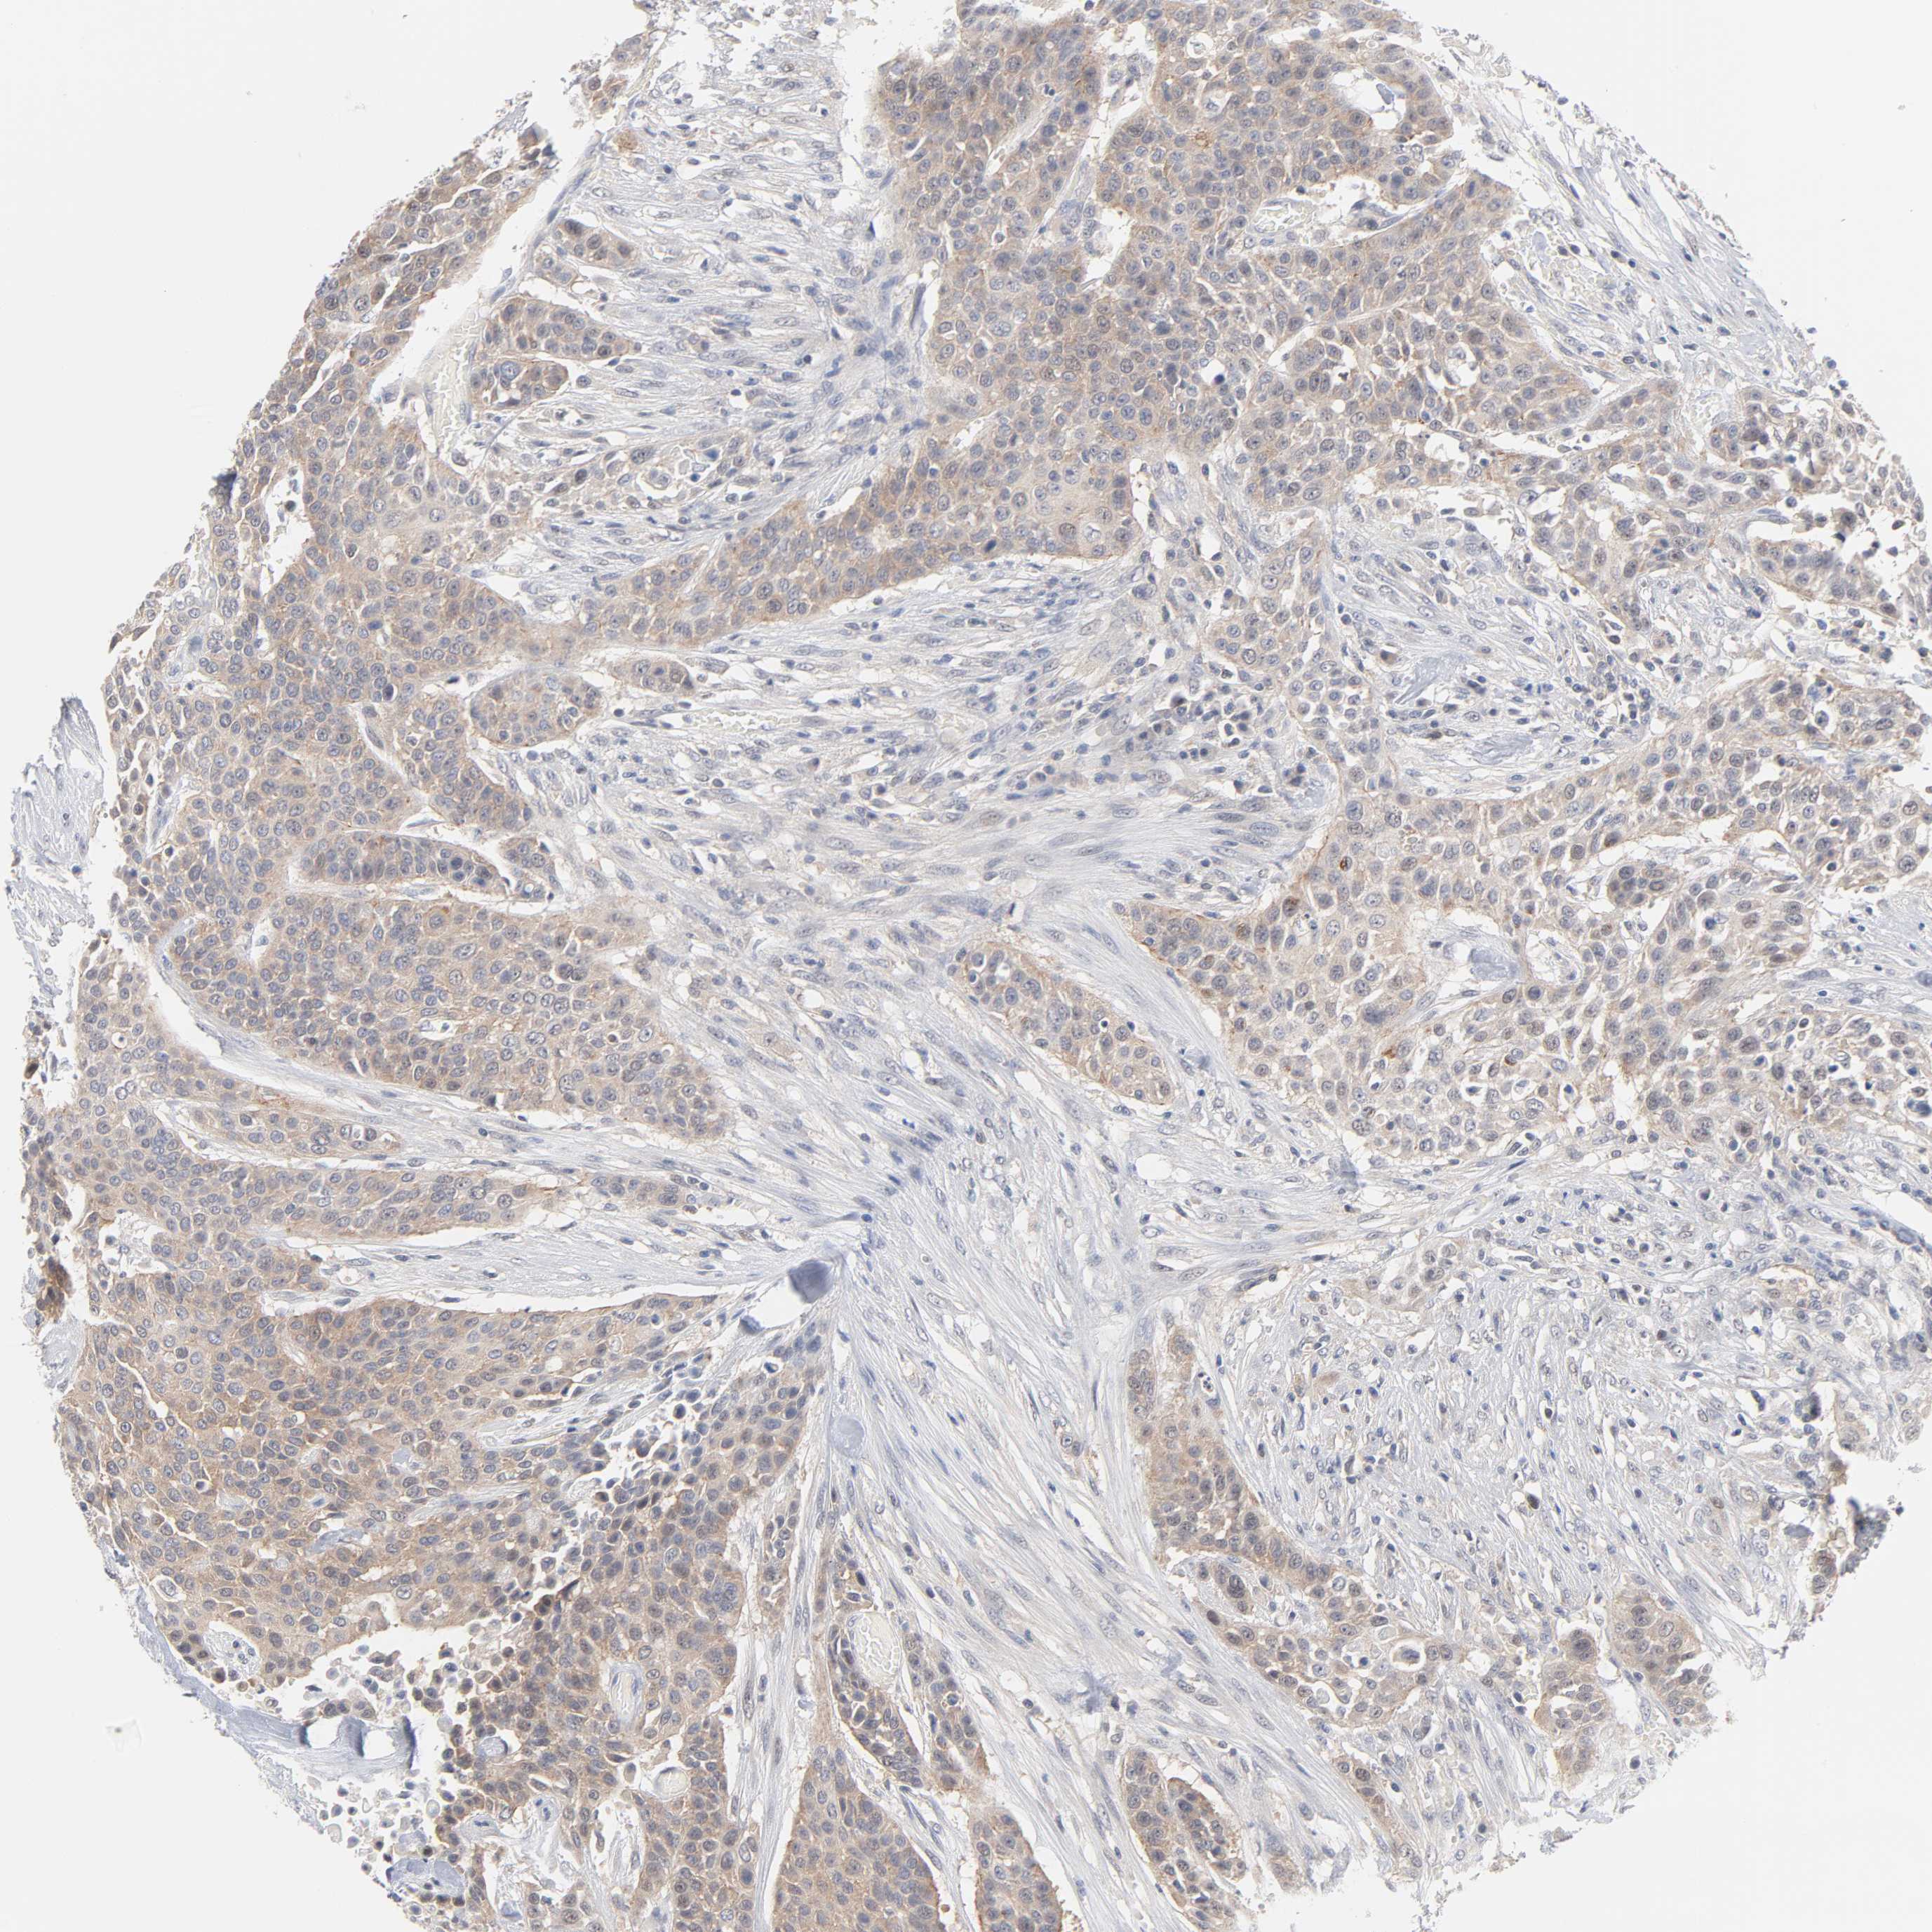

UROTHELIAL CANCER - Protein expressioni

A mouse-over function shows sample information and annotation data. Click on an image to view it in a full screen mode. Samples can be filtered based on level of antibody staining by selecting one or several of the following categories: high, medium, low and not detected. The assay and annotation is described here.

Note that samples used for immunohistochemistry by the Human Protein Atlas do not correspond to samples in the TCGA dataset.

Antibody stainingi

Antibody staining in the annotated cell types in the current human tissue is reported as not detected, low, medium, or high, based on conventional immunohistochemistry profiling in selected tissues. This score is based on the combination of the staining intensity and fraction of stained cells.

Each image is clickable and will lead to virtual microscopy that enables deeper exploration of all samples and also displays staining intensity scores, fraction scores and subcellular localization as well as patient and tissue information for each sample.

Antibody HPA003617

Staining

High

Medium

Low

Not detected

Intensity

Strong

Moderate

Weak

Negative

Quantity

>75%

75%-25%

<25%

None

Location

Nuclear

Cytoplasmic/membranous

Cytoplasmic/membranous,nuclear

Urothelial carcinoma, High grade

Urothelial carcinoma, Low grade